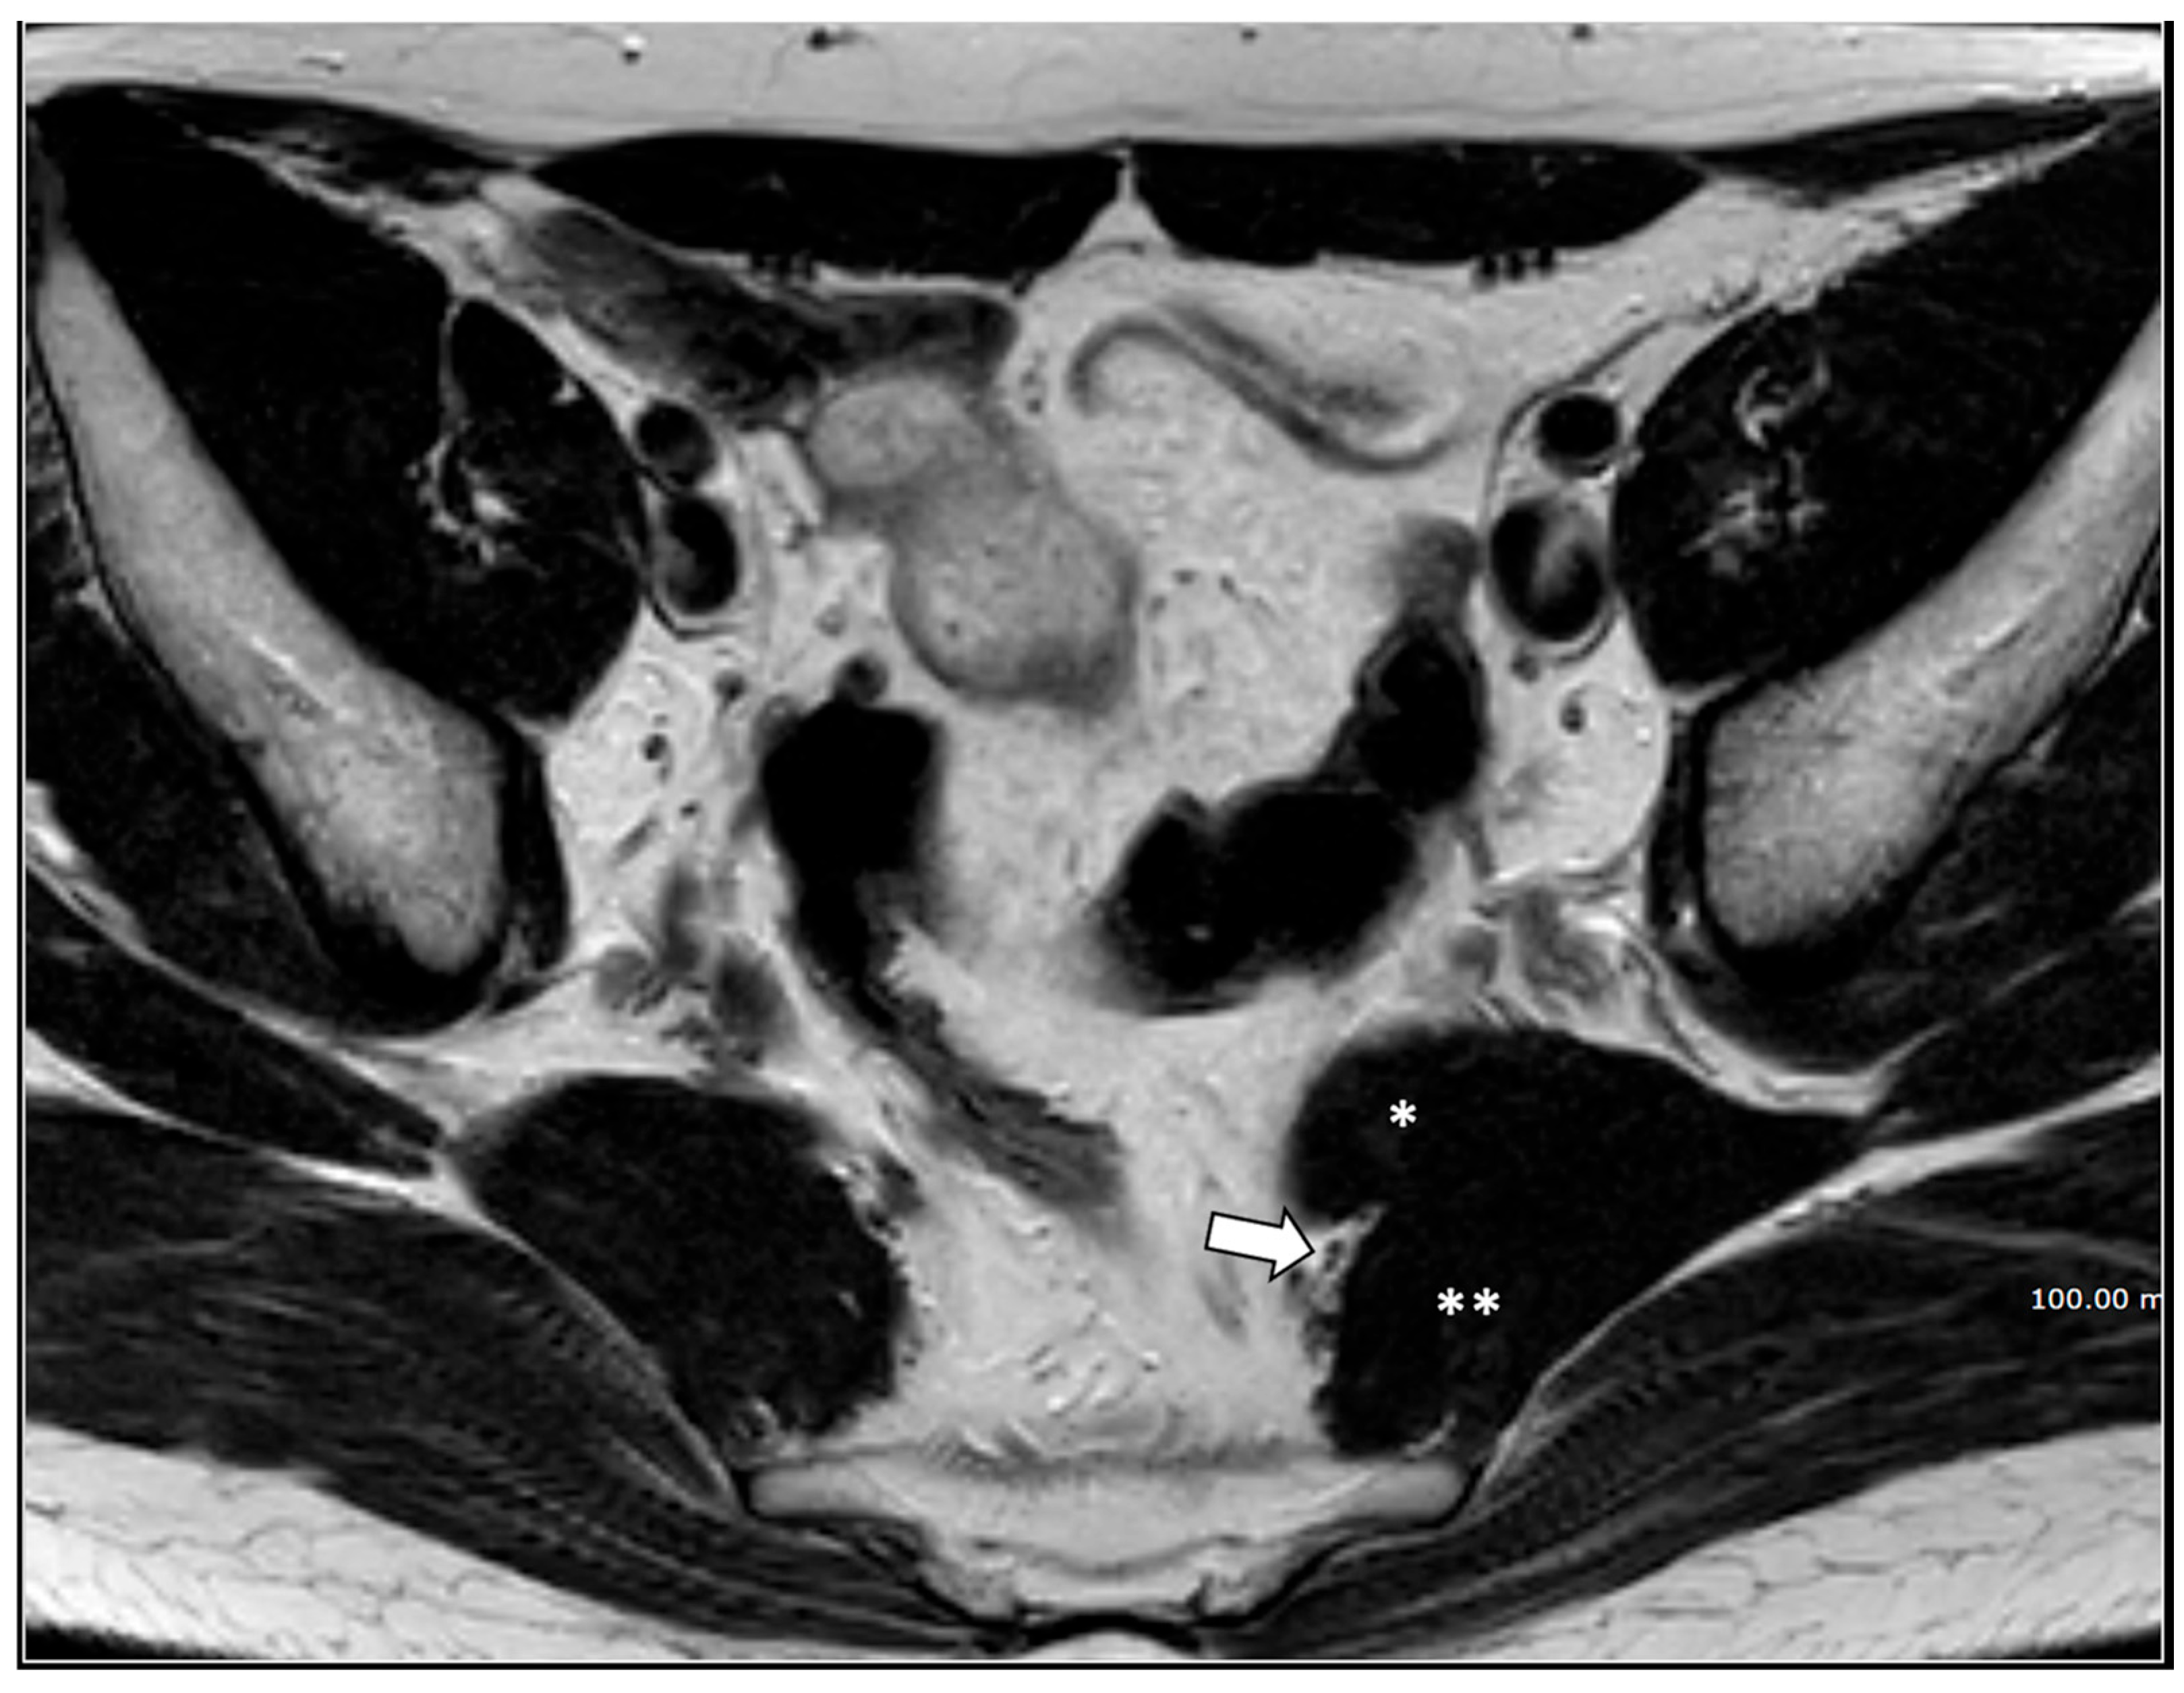

- Pudendal nerve schwannomas (2 patients);